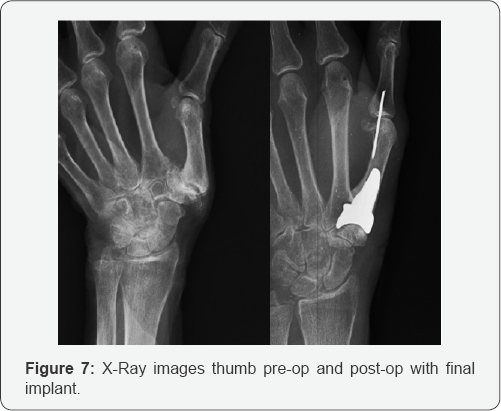

r) Once again, place the capsular elevator as a shoehorn over the trapezial articular surface and reduce the final implant. Confirm that the FCR tendon is not interposed between the implant and the trapezium. If the optional suture stabilization technique was utilized, tie the two limbs of the suture tightly over the prosethesis (Figure 7).

s) Confirm that the implant has unobstructed motion by placing the joint through a range of motion in radial abduction and opposition. This will confirm the stability of the implant as well as its kinematics. Take final fluoroscopic images of the final implant to document appropriate placement (Figure 8).